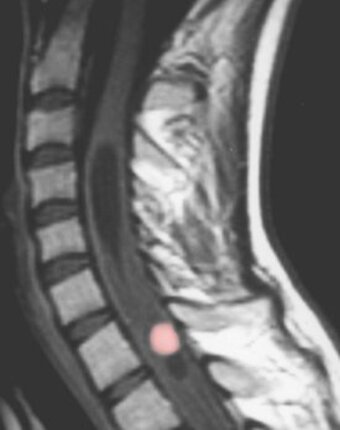

Hemangioblastomas of the central nervous system are benign tumors. They mostly occur in the posterior fossa or spinal cord. These tumors can develop sporadically or hereditarily as a manifestation of von Hippel-Lindau disease. Typically, the tumors develop an adjacent tumor-associated cyst as a small, solid formation along the wall of a large cyst. These cysts contain an amber-colored liquid and in some cases form a so-called syrinx in the spinal cord.

Symptoms of hemangioblastomas in the cerebellum mainly include headaches, nausea, incoordination, unsteady gait and dizziness. In progressive tumors it can also lead to disorders of consciousness. Patients affected by tumors of the spinal cord may develop numbness or paralysis. In addition, an unsteady gait may occur. Difficulties with defecation and urination are some of the other possible symptoms. The tumors rarely cause pain.

What is the medical treatment?

In general, the tumors grow slowly so that an annual check-up is sufficient. For the primary diagnosis and follow-up examination, an MRI with contrast is the method of choice. If treatment is necessary, the tumor is removed microsurgically. Since hemangioblastomas are benign tumors, the tumors can usually be completely removed and generally do not recur. Radiation therapy has so far provided no convincing evidence of success. Drug therapy methods are currently the subject of scientific investigation. There is currently no drug that has been shown to be effective against hemangioblastomas.